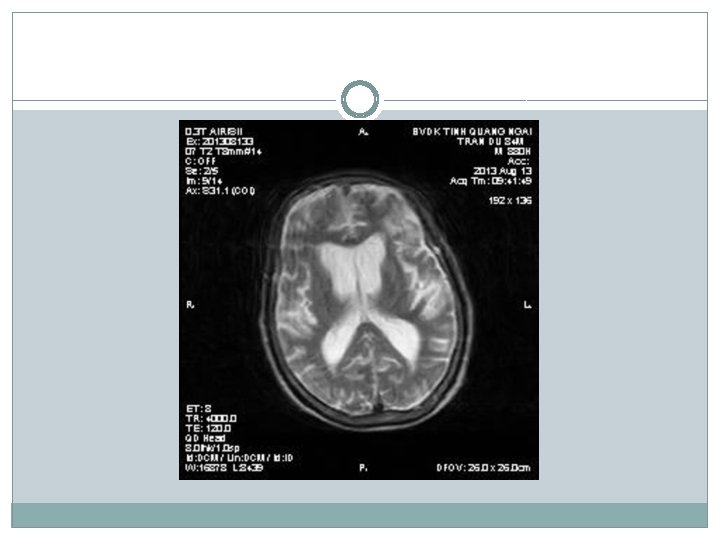

�Siêu âm có nang thận phải # 34 mm �X-quang tim phổi bình thường; thoái hóa cột sống thắt lưng �Điện não: chủ yếu sóng chậm Theta, ưu thế vùng trán (T) �Điện tim bình thường �CT scan não: Nhồi máu não thùy trán (T) �MRI não: Nhồi máu thùy trán (T), teo vỏ não thùy trán + não thất giãn nhẹ

Chẩn đoán �Dựa vào tiền sử bản thân và gia đình, quá trình bệnh lý, thăm khám lâm sàng, kết quả hình ảnh học �Dựa theo Tiêu chuẩn chẩn đoán của Hội về Bệnh Parkinson của Anh Quốc được quốc tế áp dụng cho bệnh Parkinson(United Kingdom Parkinson’s Disease Society Brain Bank Clinical Diagnostic Criteria), chúng tôi chẩn đoán: Nhồi máu não thùy trán (T)/bệnh Parkinson

Chẩn đoán �Tuy nhiên có điểm chưa phù hợp trong chẩn đoán bệnh Parkinson: khởi bệnh run cả hai bên đối xứng; hình ảnh học MRI cho thấy có teo vỏ não, có biểu hiện rối loạn tâm thần sớm